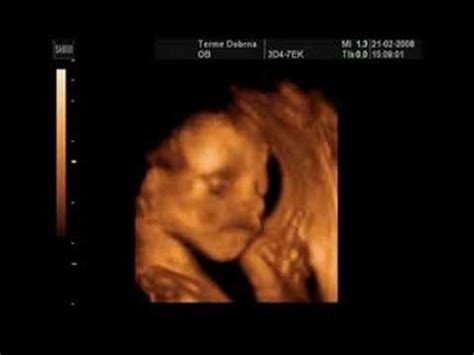

V 34. tednu nosečnosti sta dvojčka že dobro razvita, čeprav še vedno veljata za prezgodaj rojena. Njihova teža se lahko giblje okoli 1700-2000 gramov, kar je primerljivo z velikostjo buče hokaido. Otrokovo okostje še vedno absorbira kalcij, da postane čvrstejše, vendar kosti še niso povsem razvite, zato je priporočljivo uživanje dodatnega vitamina D.

Sluh dvojčkov je v tem obdobju že dobro razvit, zato lahko prepoznajo in reagirajo na enostavne pesmi, ki jim jih pojejo starši. Nekateri verjamejo, da bodo dojenčki kasneje prepoznali pesmi, ki so jih slišali med nosečnostjo, kar jim lahko olajša uspavanje. Kljub omejenemu prostoru v maternici, dvojčka še vedno intenzivno premikata svoje telo. Pri dečkih se v tem času testisi premaknejo iz trebuha v mošnjo, ki je lahko videti povečana zaradi zadrževanja vode.